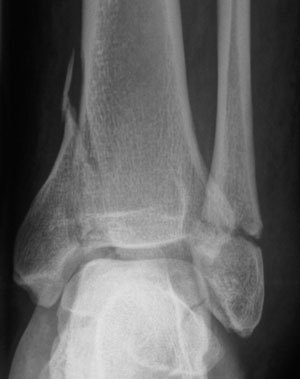

Patient consulte aux urgences pour douleurs importantes de cheville et impotence fonctionnelle après une chute. Des radios sont faites: quel diagnostic? Quel est le mécanisme lésionnel probable?

Fracture bimalléolaire de cheville sous-tuberculaire

mécanisme en aDduction forcée